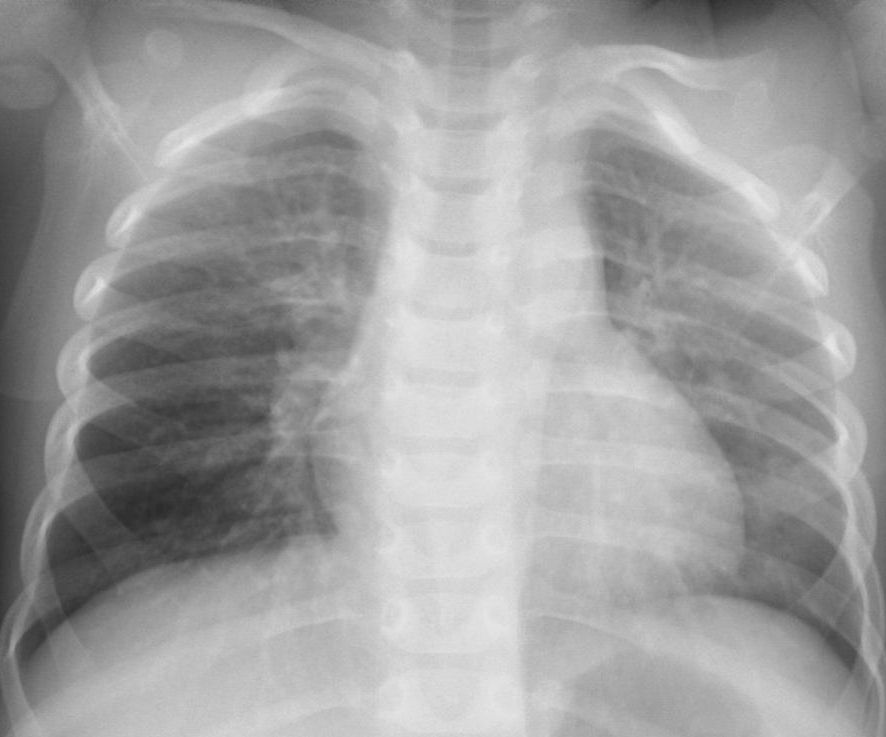

60代、微熱軽度の息苦しさ発病後7日目(COVID-19軽症)